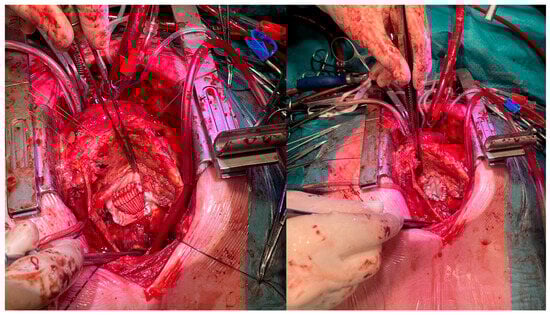

The patient was scheduled dated 18 March 2024 for urgent surgery. After median resternotomy, cardiopulmonary bypass was installed using central aortic cannulation and right femoral vein and superior caval vein canulation; the inferior vena cava was inaccessible due to the pseudoaneurysm. After dissecting the heart, the aneurysm was opened at arrested heart. After debridement and removal of the dehiscent patch material, the neck of the aneurysm in the inferior wall could be visualized and reconstructed using a Dacron patch (3 × 4 cm), which was subsequently covered with a large xenopericardial patch for hemostatic purposes, as seen in Figure 4. No histological examination of the resected pseudoaneurysm was conducted, as it was not deemed necessary for clinical decision-making. Additionally, a restrictive mitral annuloplasty using an Edwards Physio ring (size 28, downsized by 2 ring sizes) and TVP (using a size 30 Edwards Physio Tricuspid annuloplasty ring) was performed.

Figure 4. On the left side, the closure of the LV with the Dacron patch; on the right side, the Dacron patch overlayed with xenopericardial patch.